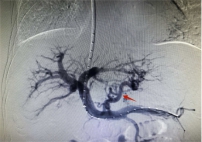

随着手术方案的敲定,张爷爷随之转入介入血管外科,团队完成充分术前评估与准备工作后,在杨维竹教授的带领指导下,介入外科团队依托精准影像导航技术,通过患者颈部微小穿刺点,将导管精准送达目标血管。团队以精细操作完成肝内分流通道的构建,同时对出血责任血管进行致密栓塞,整个手术耗时不足1小时,过程顺利。术后患者门静脉压力显著下降,止血、减压效果立竿见影。